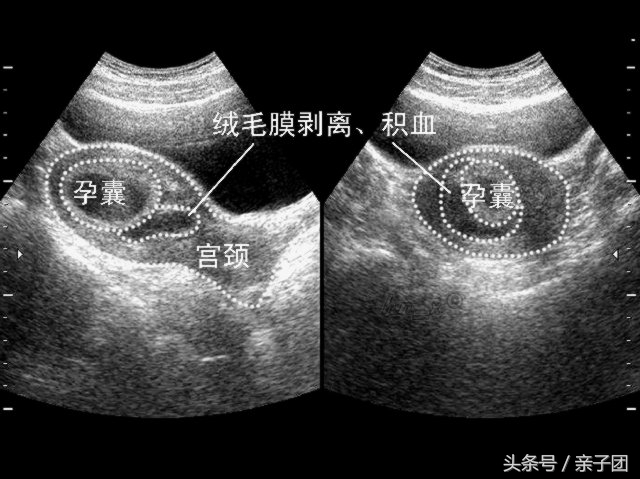

孕早期阴道出血最常见的原因就是:流产。流产开始时一般阴道出血比较少,常为暗红色的或者咖啡色的分泌物,有时候会伴有下腹隐痛,是为先兆流产。这时如果及时去医院经过医生处理及休息,多数情况下症状消失,可以继续怀孕。但是如果症状加重,出血增多,下腹痛明显,甚至阴道排出肉样的组织物,这时说明胚胎已经流出,流产是不可避免了。虽然看到肉状组织也就是胚胎已经排出,为了安全起见,还是要去医院检查,根据检查结果让医生决定要不要做清宫手术。

孕早期阴道出血最危险的就是:宫外孕。宫外孕:就是指受精卵没有着床在子宫内膜,而是在子宫内膜以外的组织,95%的宫外孕发生于输卵管。为什么说宫外孕危险,因为随着胚胎的发育,输卵管支持不了日益长大的胚胎,绒毛穿透输卵管壁,引起管壁破裂,出现肚子里面大量的出血,可引起休克,甚至死亡,而这个时候阴道出血的量仍不会很多。特别是有过盆腔感染病史、做过宫腔手术、做过输卵管手术的妇女,更加应该警惕。

所以我们在确认怀孕后都会去医院照B超,早期照B超,就是为了确认胚胎是在子宫内着床还是子宫外着床。